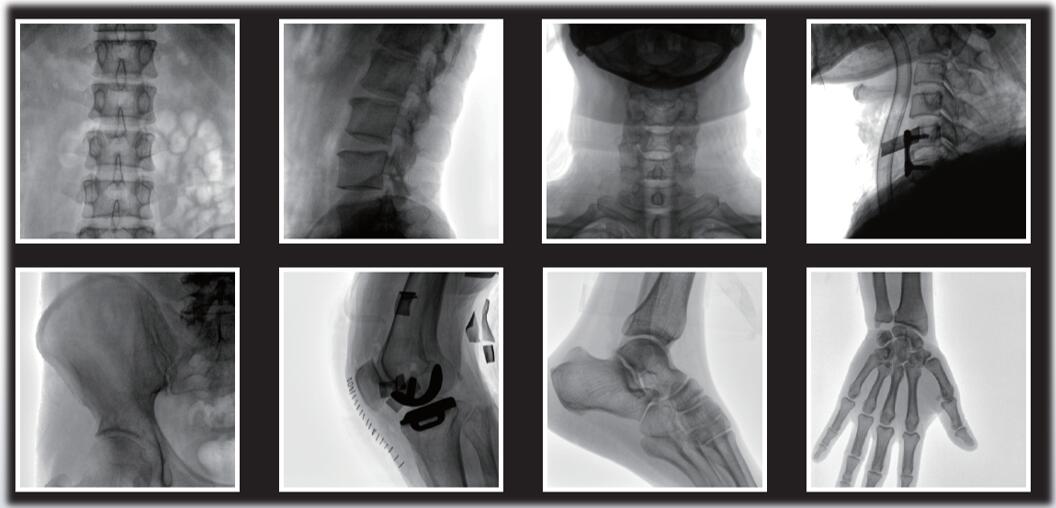

你知道什么是平板小C臂嗎?說起平板小C臂,大家印象大多是圖像清晰、電動(dòng)控制、大開口廣闊空間、顏值高等。確實(shí),平板小C臂相較于傳統(tǒng)影增小C,有著獨(dú)特的優(yōu)勢(shì)。普愛醫(yī)療PLX118WF系列移動(dòng)式平板C形臂X射線機(jī)是國產(chǎn)平板小C的代表品牌,其全電動(dòng)運(yùn)動(dòng)機(jī)架、智能算法高清晰度圖像及超低輻射劑量,是數(shù)字骨科新技術(shù)覆蓋基層醫(yī)院的必備設(shè)備,也是近些年市場(chǎng)主流C形臂設(shè)備。

平板小C臂在骨科手術(shù)中的定位、診斷、微創(chuàng)手術(shù)的開展與治療中發(fā)揮獨(dú)特的作用。普愛醫(yī)療的PLX118系列平板小C臂優(yōu)勢(shì)特點(diǎn)如下:

大尺寸動(dòng)態(tài)平板探測(cè)器,圖像清晰細(xì)膩,滿足臨床多種檢查。

采用了多分辨率圖像增強(qiáng)處理技術(shù),不同部位不同圖像處理。

作為一名醫(yī)生,您需要清晰的圖像質(zhì)量來幫助您應(yīng)對(duì)更具挑戰(zhàn)性的介入治療。PLX118系列平板小C臂為您提供優(yōu)質(zhì)的圖像、靈活的操作體驗(yàn)和更低的劑量表現(xiàn)。如果您想采購,或了解產(chǎn)品具體參數(shù),歡迎咨詢